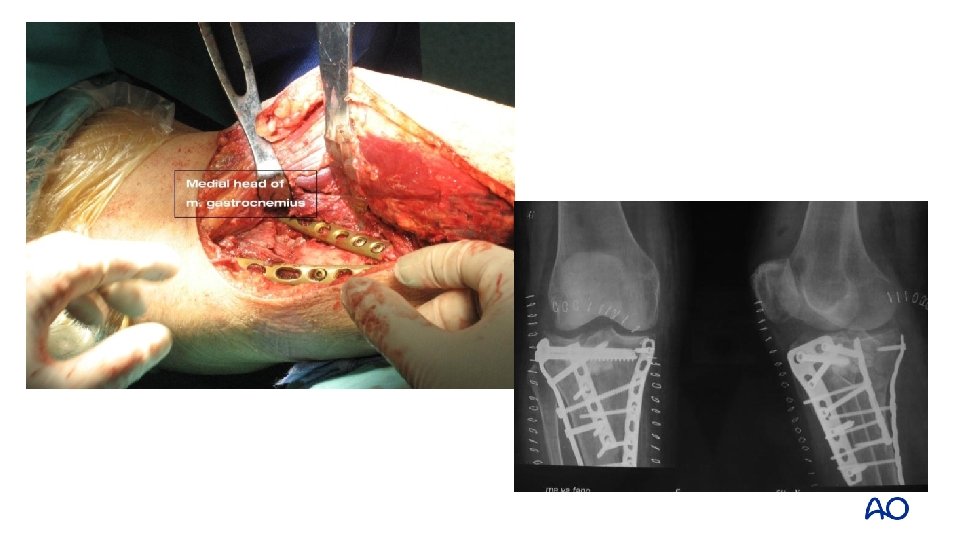

Schatzker type IV: 2 -column fracture—flexion varus Varus flexion mechanism medial posterior

Approach: midline and posteromedial

Midline approach Fracture window Posteromedial approach